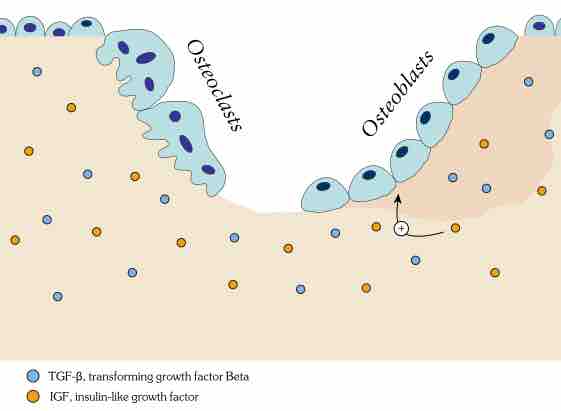

Bone remodeling or bone turnover is the process of resorption followed by replacement of bone and occurs throughout a person's life.